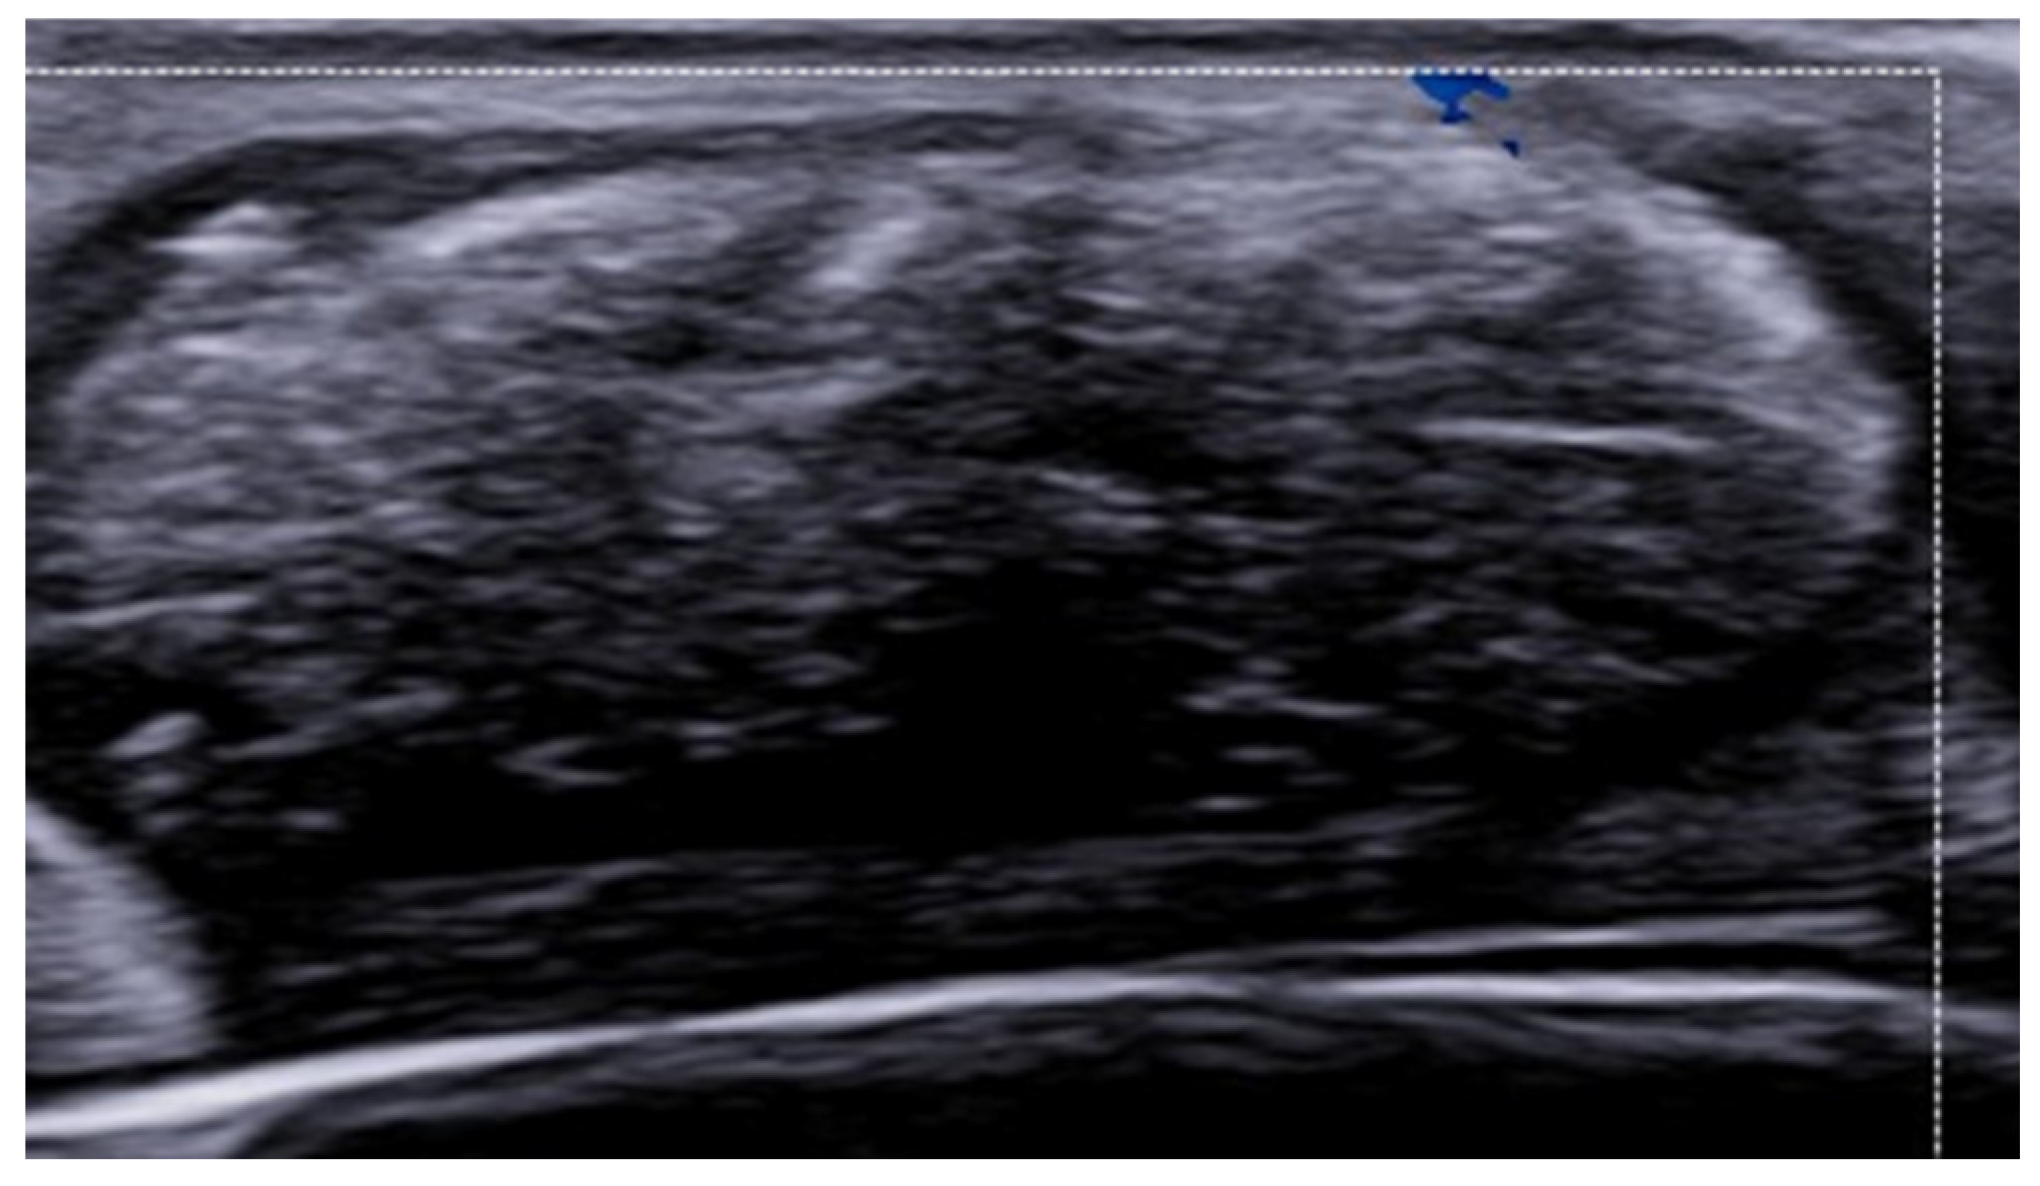

7. External-Agent-Associated Disorders